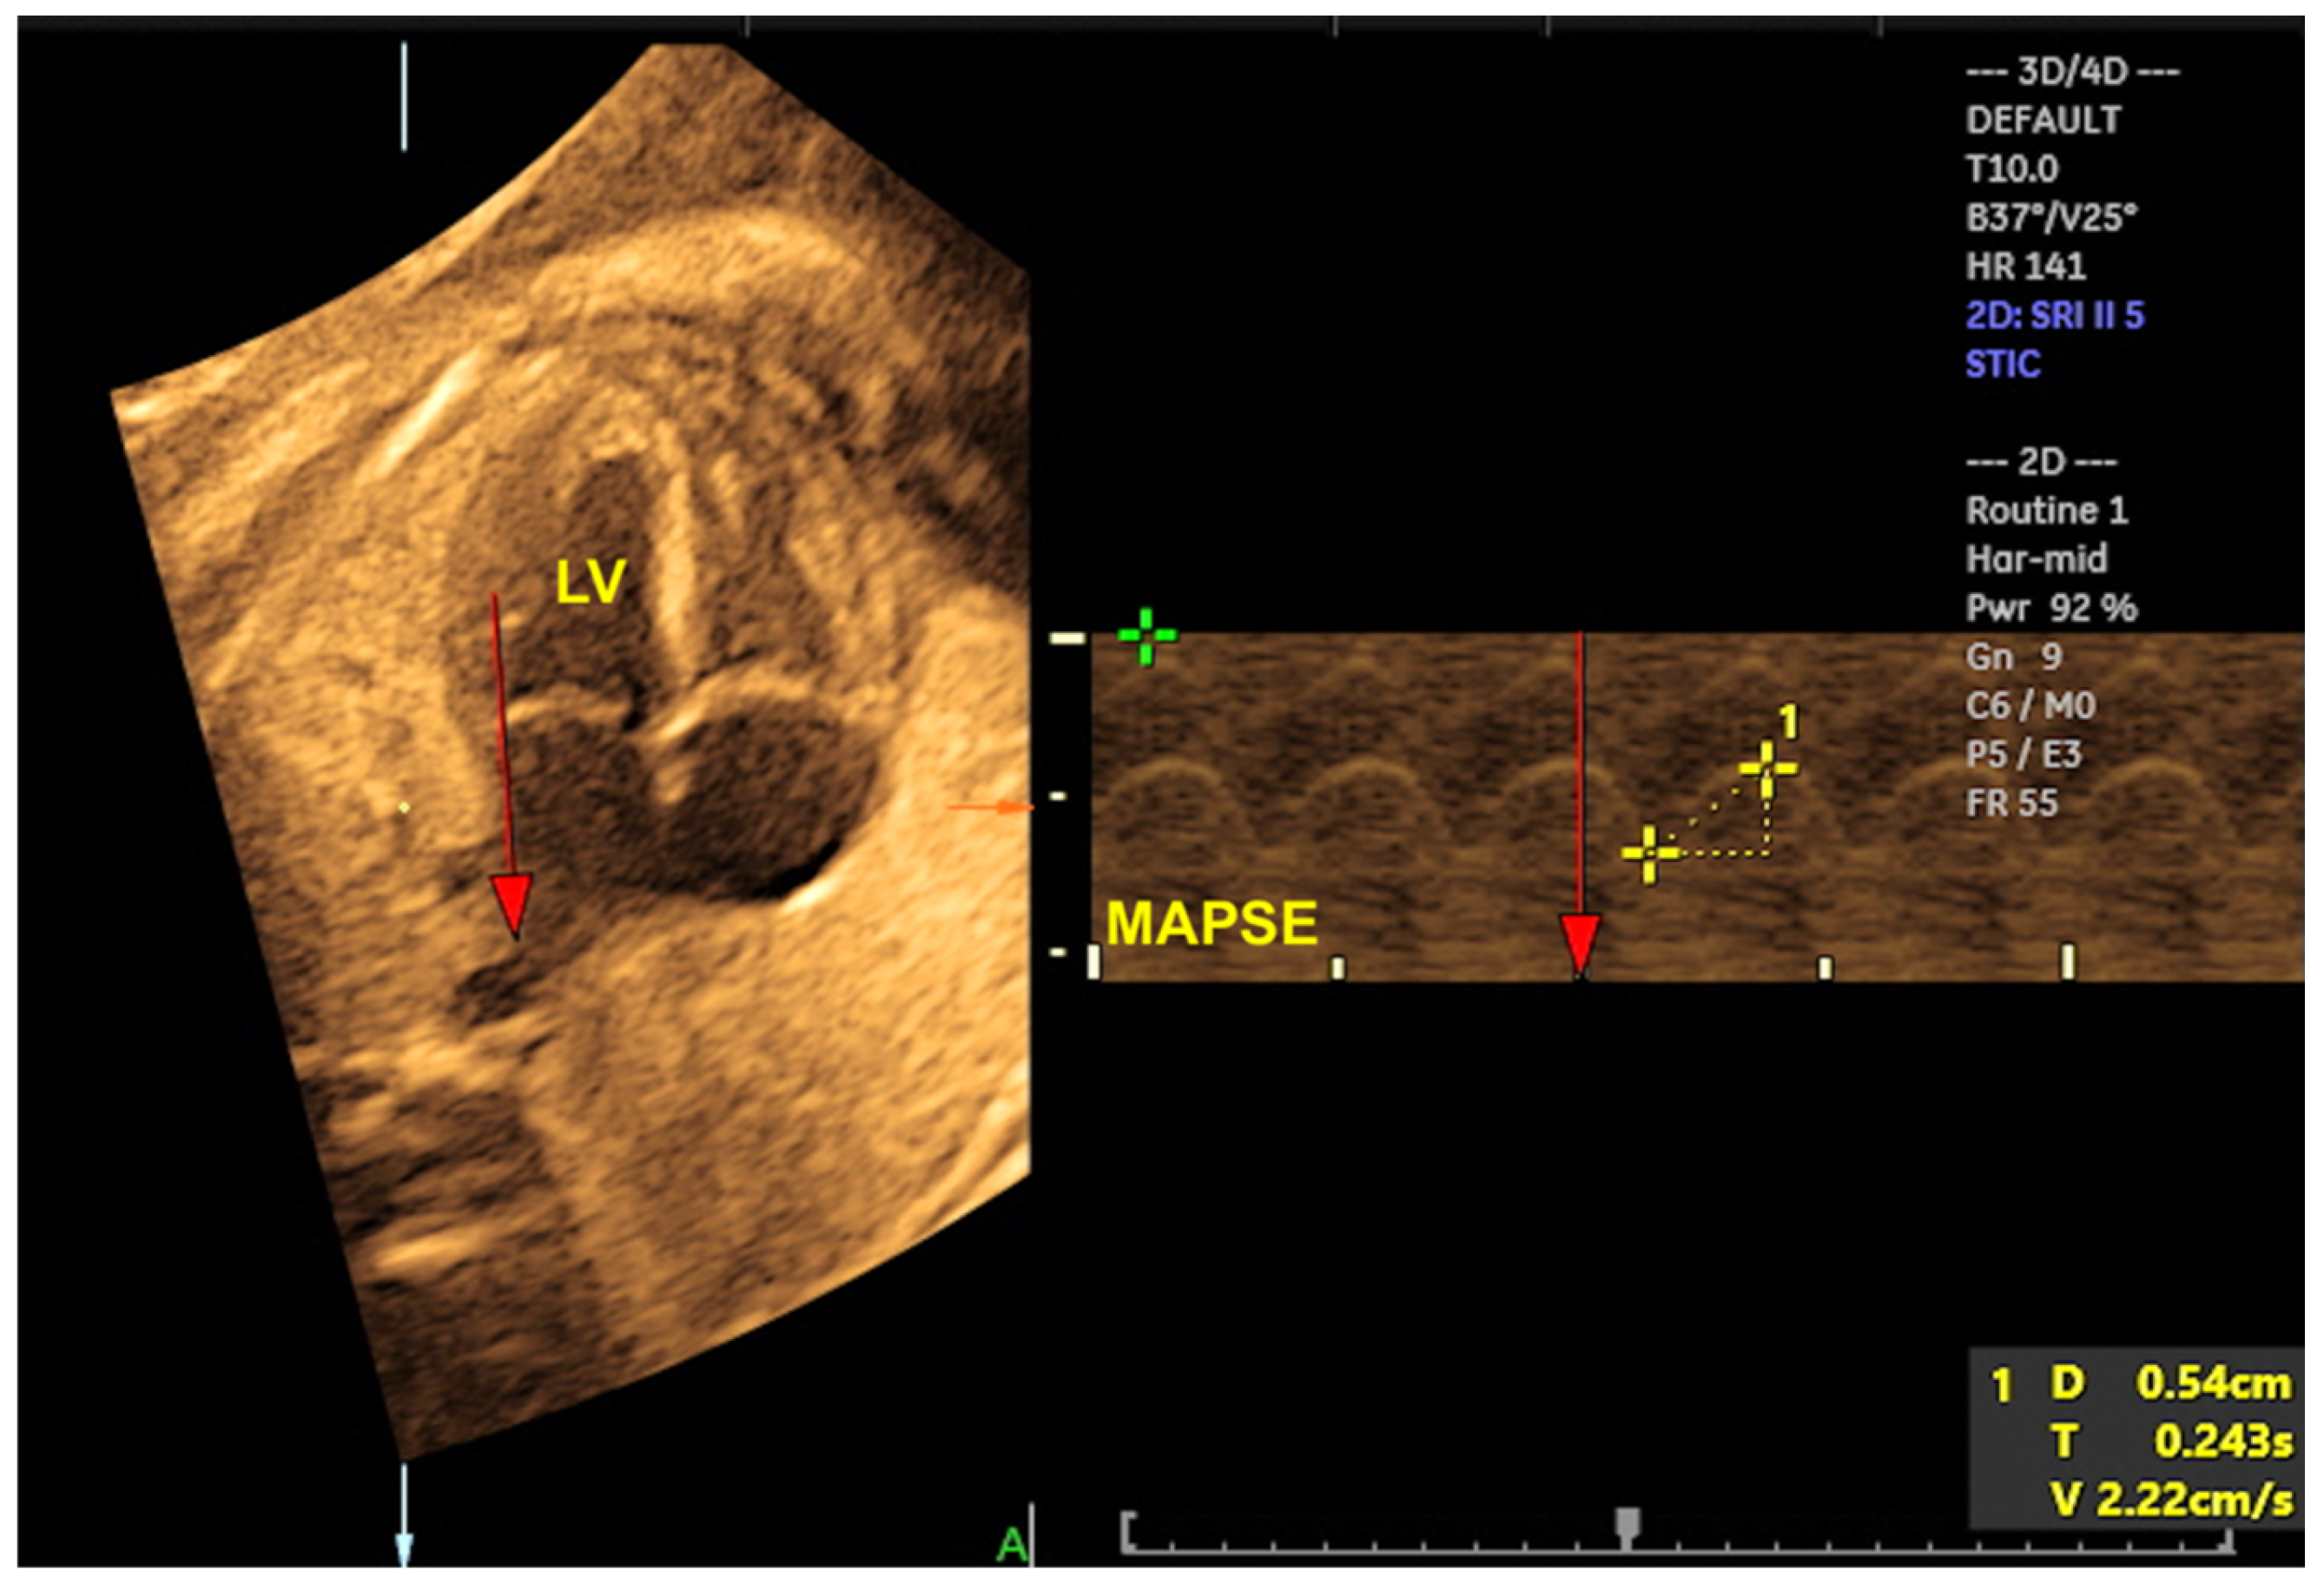

- Tanis JC, Mohammed N, Bennasar M, Martinez JM, Bijnens B, Crispi F; et al. Online versus offline spatiotemporal image correlation (STIC) M-mode for the evaluation of cardiac longitudinal annular displacement in fetal growth restriction. J Matern Fetal Neonatal Med. 2018 Jul;31(14):1845-1850.